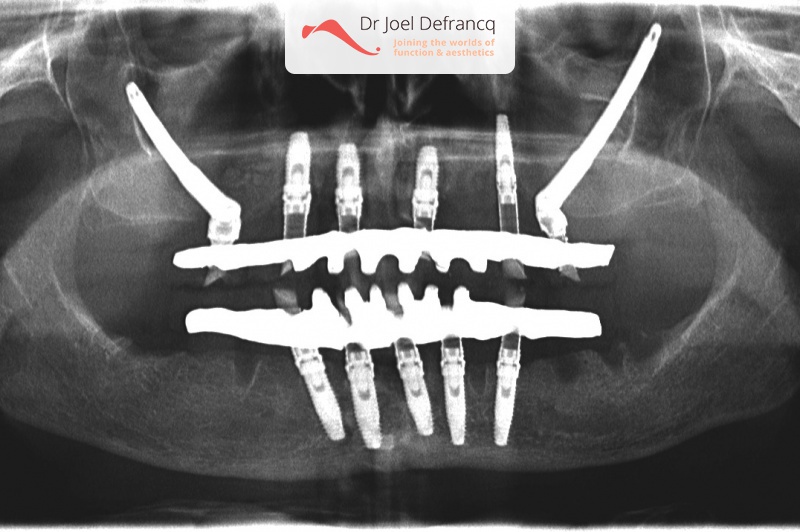

Dentale diagnose

- Klasse I

Behandeling tandheelkundige implantaten

- Vaste tanden op implantaten (bovenkaak)

- Vaste tanden op implantaten (onderkaak)

- Zygoma implantaten